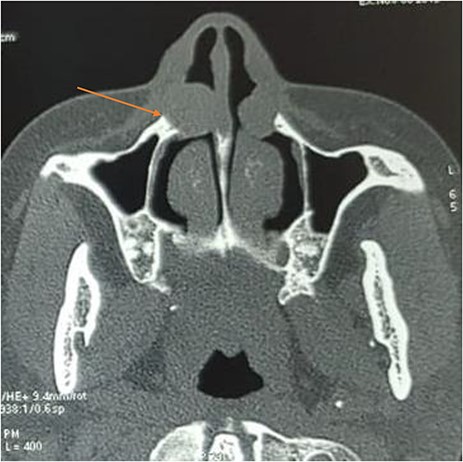

Computed tomography without injection showed bilateral mass on the inferior nasal alar region, measuring 2.1 × 2.2 × 1.9 cm on the right side and 1.7 × 1.5 × 1.2 cm on the left side. The masses were rounded, well defined and exhibiting soft tissue density. There was mass effect upon the maxilla causing scalloping on the right side (Fig. 1).

Axial computed tomography showing a bilateral well-defined, hypodense, extraosseous lesion near the ala nasi; note the cortical scalloping on the right side (arrow).